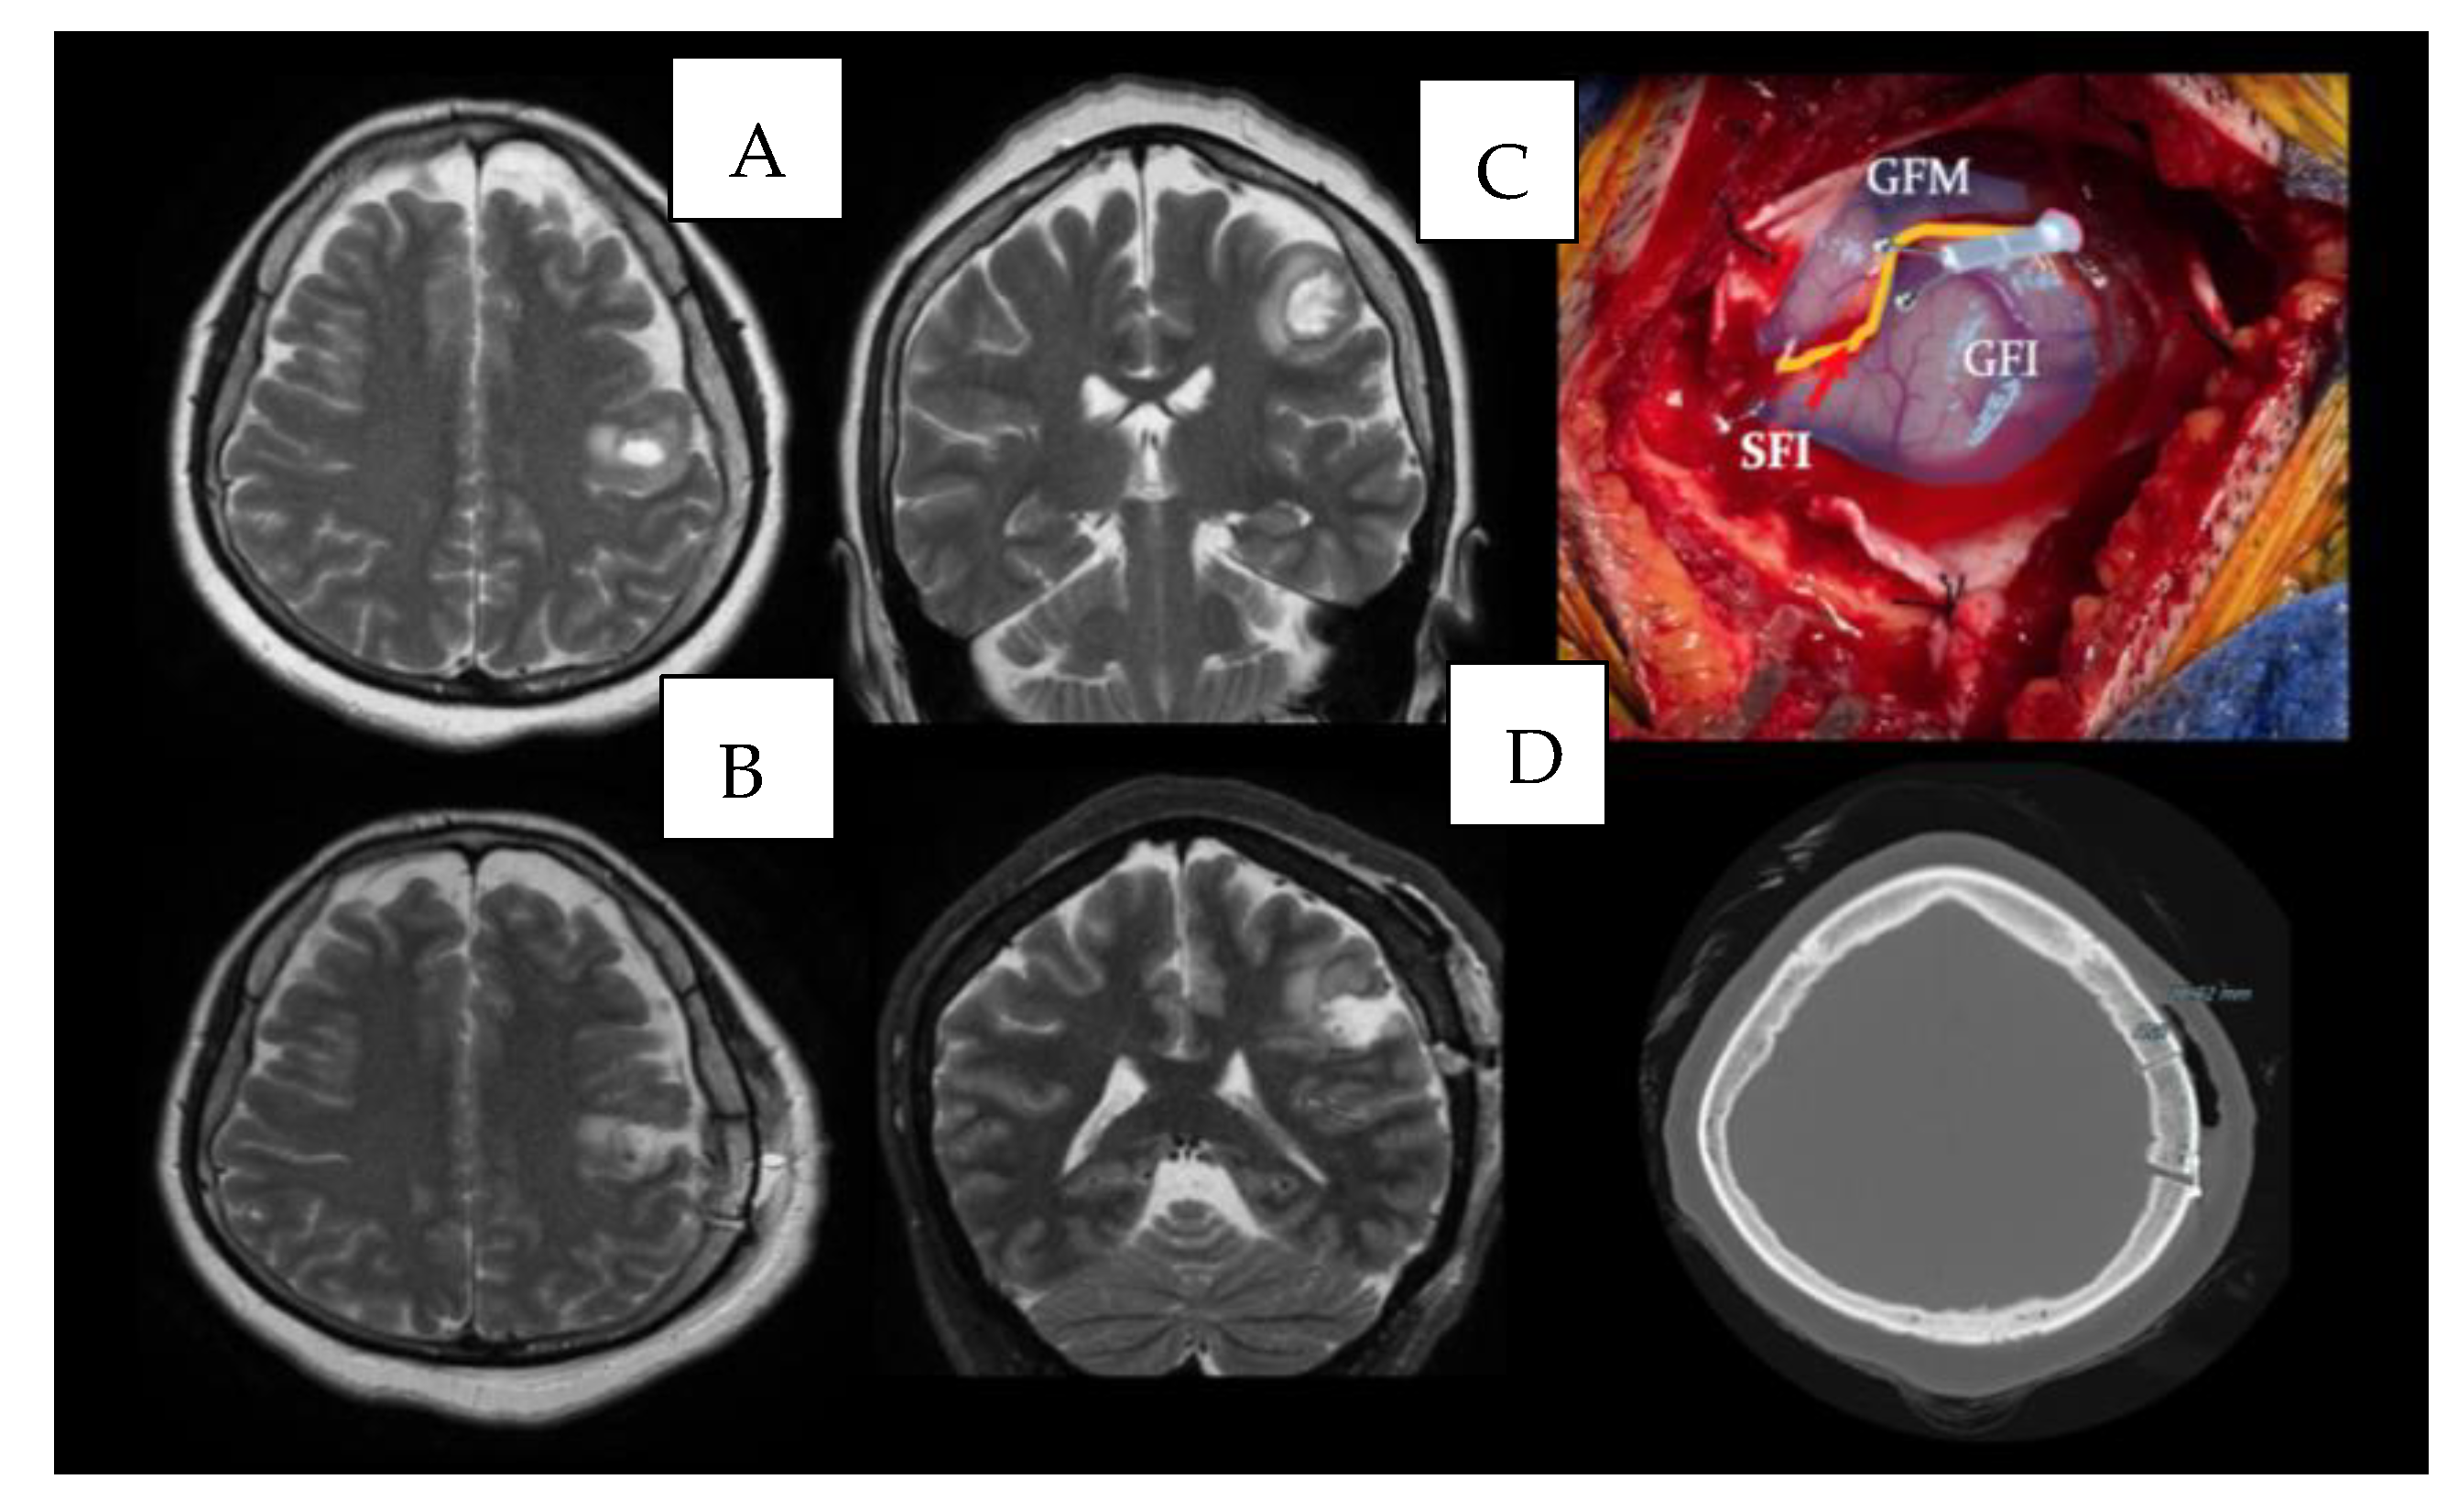

4.2. Case 2

4.3. Surgical Nuances